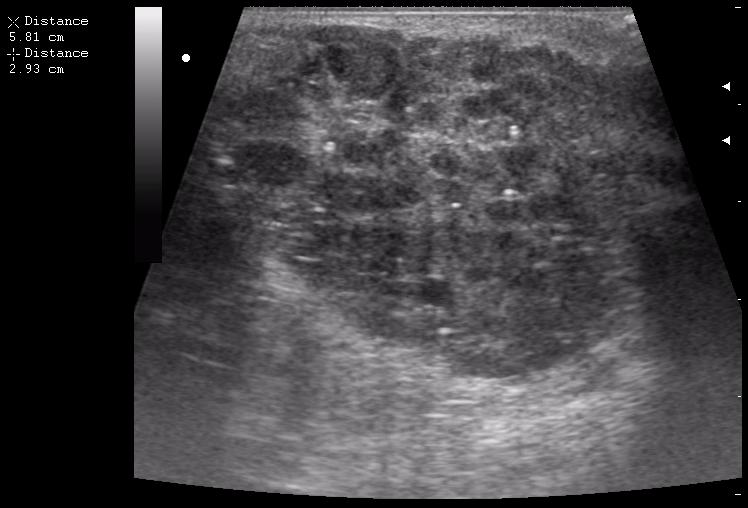

левая околоушная железа

левая поднижнечелюстная железа